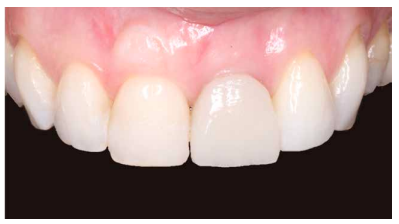

A los 4 meses se evidenció una correcta estabilidad del IOI fruto de un correcto proceso de osteointegración. Respecto a los tejidos blandos, se podía observar una disminución del volumen de la papila interdental (Figura 21). Dada la ausencia de signos y síntomas y la correcta osteointegración del IOI, se realizó la modificación del perfil subcrítico con el fin mejorar la disposición del tejido blando gingival y favorecer la recuperación de dicha papila (Figuras 22 y 23).

A los 6 meses se puede observar una correcta disposición de los tejidos blandos, así como la estabilidad de estos en el tiempo debido al manejo de los mismos a través de la prótesis provisional (Figura 24). Se realizó además un control radiológico para conocer el estado de los tejidos duros (Figura 25).